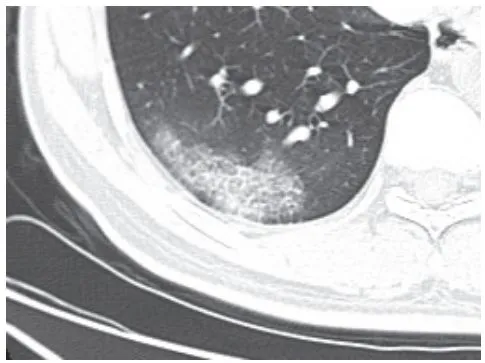

二、进展期征象

新冠肺炎大多数病例进展迅速,复查 CT 影像发生明显变化

表现为病灶数目明显增多,范围明显扩大,密度增高,病灶分布由外周向中央推进

根据既往 SARS 病理学机制,提示为肺泡腔内聚集大量细胞渗出液、间质内血管扩张渗出;肺泡连通起来形成融合态势(图 2-11)

图 2-11 病灶数目增多、范围扩大 (A-D)